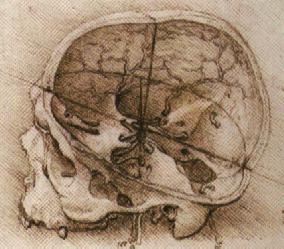

la base du crâne est séparée en trois étages anatomiques : antérieur, moyen, et postérieur, recoupant les os formant la base : frontal, ethmoïde, sphénoïde, temporal, et occipital ; ces os sont réunis par des sutures et parcourus de foramens laissant passage aux vaisseaux, placodes sensorielles et nerfs crâniens.

- étage antérieur : correspondant à la portion basale de l’os frontal qui constitue le toît d’orbite latéralement, descendant en dedans vers les gouttières olfactives de l’éthmoïde avec l’apophyse crista-galli au centre, il est en rapport avec les cavités aériennes du sinus frontal, qui se développe à l’adolescence, de l’ethmoïde, qui est déjà pneumatisé à la naissance, et qui continue de se développer jusqu’à l’adolescence

- étage moyen : correspondant à la grande aile du sphénoïde et à la face supérieure du rocher, il est en rapport avec le sinus sphénoïdal, qui commence à apparaître vers 2 ans ; le canal optique est particulièrement exposé par la finesse de ses parois inférieure et interne, qui font une saillie dans la cavité des sinus.